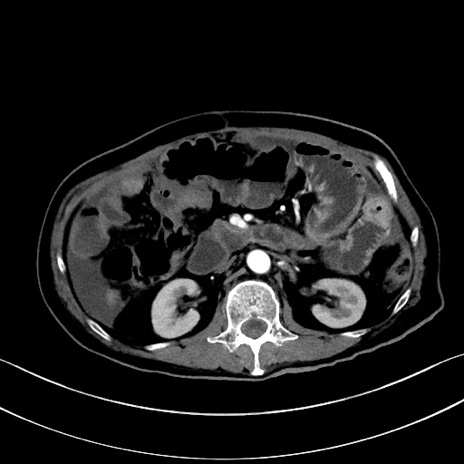

症例28(横断像)

【症例】60歳代男性

【主訴】嘔吐

【現病歴】胃癌にて胃全摘後。食思不振が悪化し、夜中に嘔吐することがある。

【既往歴】胃癌、胃全摘、脾摘、胆摘後

【データ】WBC 5900、CRP 10.56